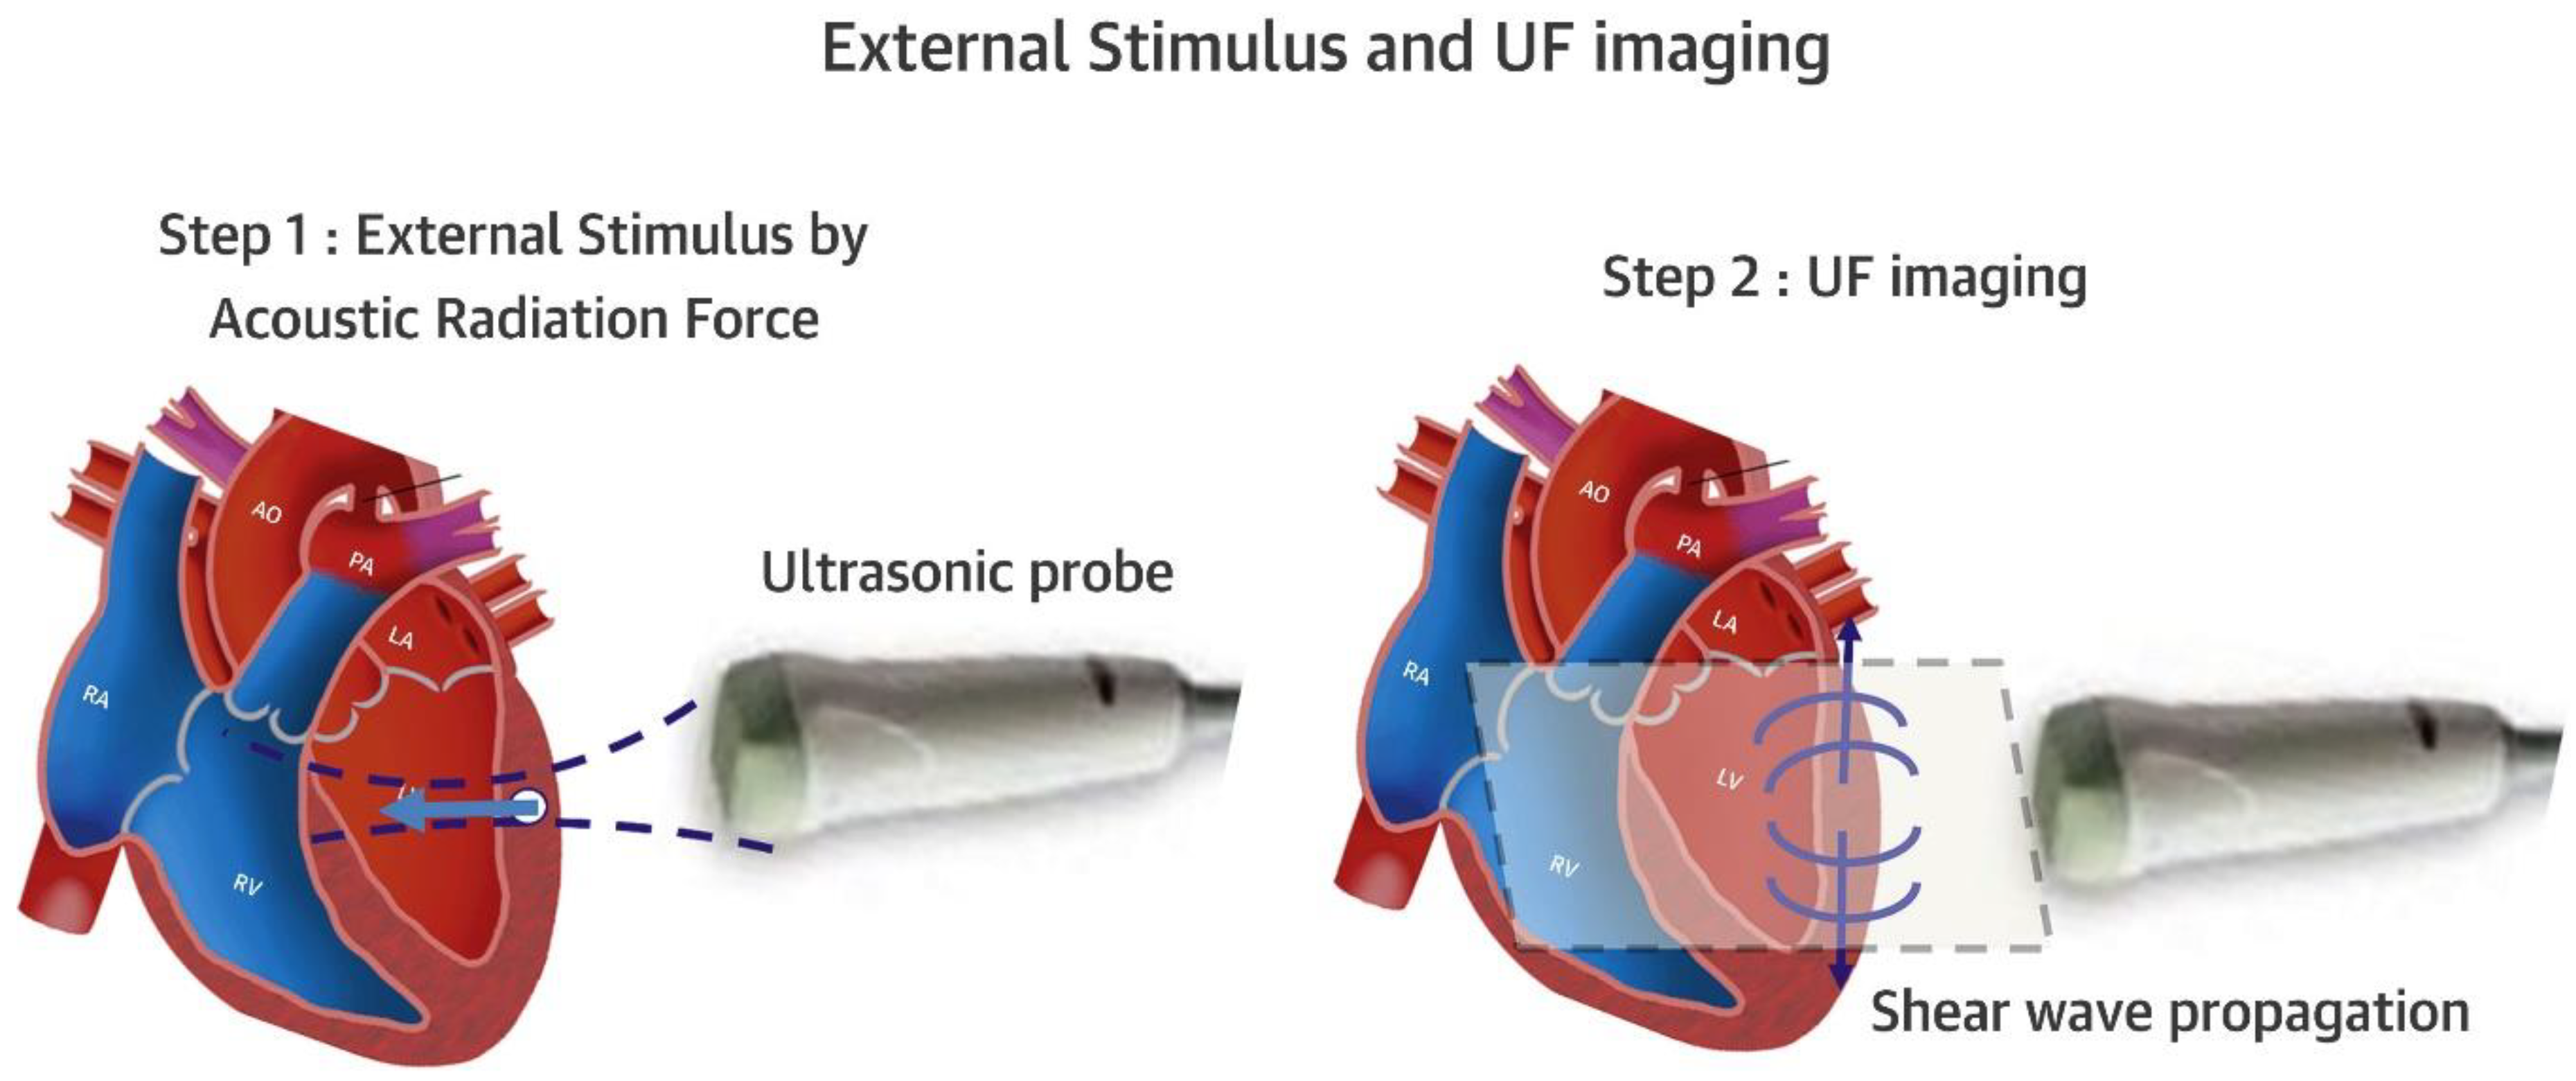

- Villemain, O.; Correia, M.; Mousseaux, E.; Baranger, J.; Zarka, S.; Podetti, I.; Soulat, G.; Damy, T.; Hagège, A.; Tanter, M.; et al. Myocardial stiffness evaluation using noninvasive shear wave imaging in healthy and hypertrophic cardiomyopathic adults. J. Am. Coll. Cardiovasc. Imaging 2019, 12, 1135–1145. [Google Scholar] [CrossRef] [PubMed]

- Villemain, O.; Baranger, J.; Friedberg, M.K.; Papadacci, C.; Dizeux, A.; Messas, E.; Tanter, M.; Pernot, M.; Mertens, L. Ultrafast Ultrasound Imaging in Pediatric and Adult Cardiology. Techniques, Applications, and Perspectives. JACC Cardiovasc. Imaging 2020, 13, 1771–1791. [Google Scholar] [CrossRef] [PubMed]